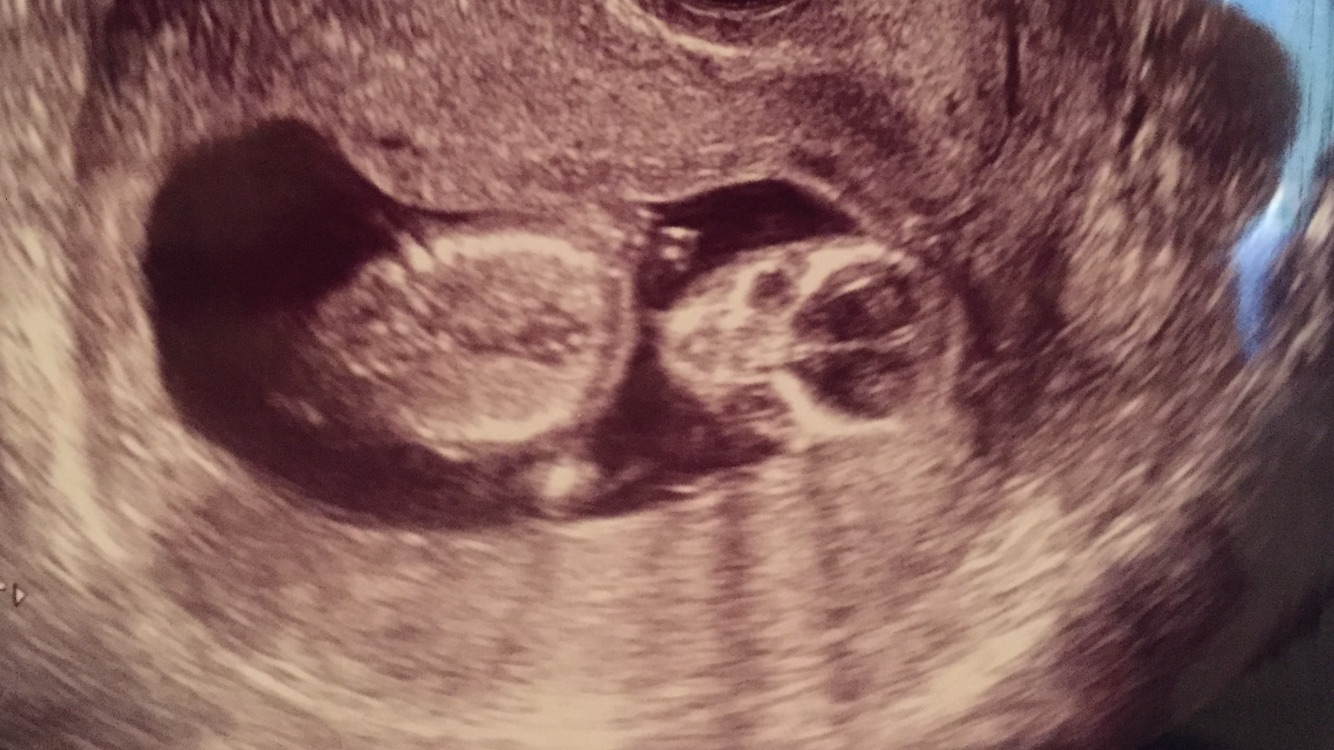

Then the next ultrasound was this past Monday (10 weeks 6 days) and baby was so big! Sleeping at first and then made the meanest face when the tech woke baby up! My husband and I loved it!